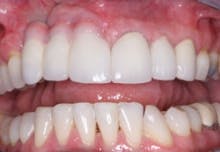

FIG. 7 — Finished restorative treatment.

When the lips of this patient are retracted, the esthetic result is unacceptable (Fig. 7). However, when the patient smiles as high as he can, the result is optimal, and he is very satisfied with his treatment (Fig. 8).

FIG. 8 — Retracted lips and patient’s smile.